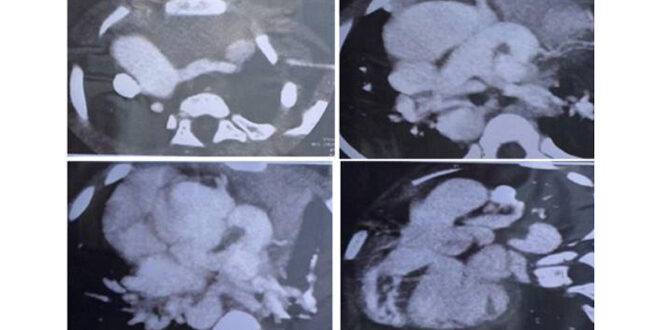

وأوضحت كنعان أنه تم تأكيد التشخيص من خلال إجراء صورة طبقي محوري متعدد الشرائح، وقثطرة قلبية أظهرت وبشكل واضح المنشأ الشاذ للشريان الإكليلي الأيسر من الشريان الرئوي.

وأشارت الدكتورة كنعان إلى أن الحالة تؤكد على ضرورة الدراسة المعمقة لكل الآفات القلبية المعقدة، وعدم التغاضي عن أي جزء من الدراسة، والتأكيد على دراسة منشأ الشرايين الإكليلية والشك الكبير بوجود منشأ شاذ في حال عدم وجودها في موقعها الطبيعي، والاستعانة بوسائل تشخيصية أخرى لتأكيد التشخيص “تصوير طبقي محوري – المرنان القلبي – القثطرة القلبية”، لافتة إلى أن هذه الحالات المعقدة تتطلب خبرة جراحية عالية بسبب تعدد التشوهات الموجودة والاختلاطات المتوقعة بعد الجراحة ولا سيما نقص التروية القلبية التالي لإعادة زرع الشريان الإكليلي الأيسر.